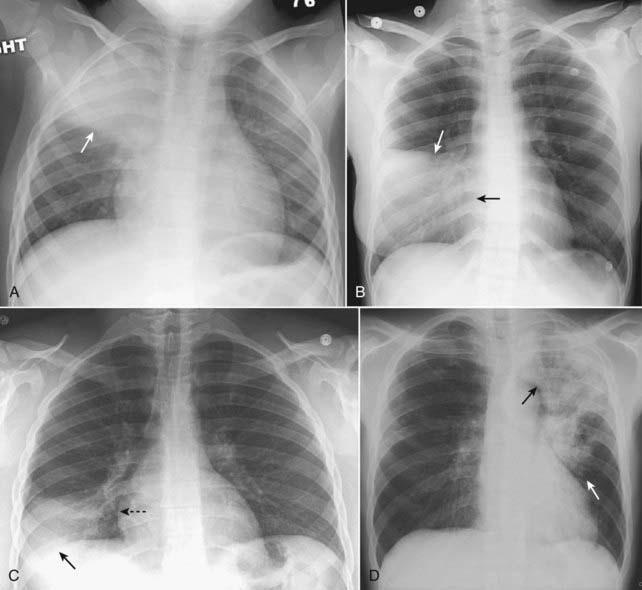

image image

Figure 7-12 Composite appearances of lobar pneumonias.

A, Right upper lobe. The disease obscures (silhouettes) the ascending aorta. Where it abuts the minor fissure, it produces a sharp margin (white arrow). B, Right middle lobe. The disease silhouettes the right heart border (solid black arrow). Where it abuts the minor fissure, it produces a sharp margin (solid white arrow). C, Right lower lobe. The disease silhouettes the right hemidiaphragm (solid black arrow). It spares the right heart border (dotted black arrow). D, Left upper lobe. The disease is poorly marginated (solid white arrow) and obscures the aortic knob (solid black arrow). E, Lingula. The disease silhouettes the left heart border (solid black arrow) but spares the left hemidiaphragm (dotted black arrow). F, Left lower lobe. The disease obscures the left hemidiaphragm (dotted black arrow) but spares the left heart border (solid black arrow).